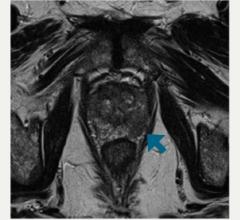

Physicians at University Hospitals Seidman Cancer Center (Cleveland) have started a clinical trial using a new form of stereotactic body radiotherapy (SBRT) to deliver radiation to a specific area of a cancerous prostate instead of the entire gland.